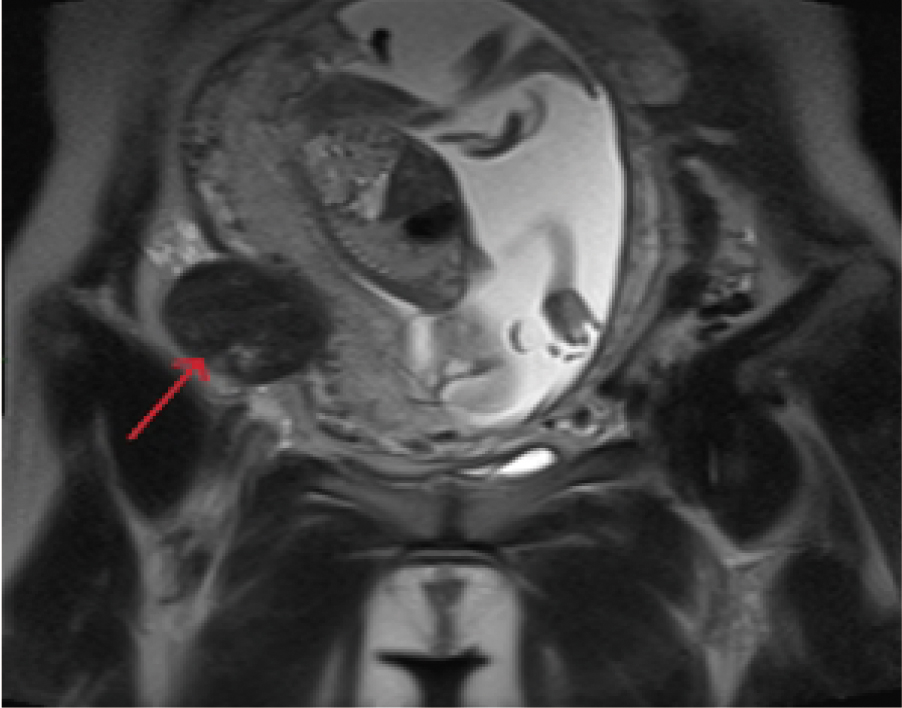

子宫肌瘤在妊娠期间出现蒂扭转或红色变性可引起腹痛并诱发流产,药物保守治疗被认为是金标准,若腹痛不能缓解,必要时于妊娠期行手术治疗。手术可根据子宫肌瘤类型、大小、位置、孕周及医生经验选择开腹或腹腔镜剔除肌瘤,但是单孔腹腔镜剔除妊娠中期子宫肌瘤少有报道。报道1例妊娠中期多发子宫肌瘤变性导致先兆流产的病例,患者经磁共振成像评估为Ⅵ型子宫肌瘤,保守治疗失败后行单孔腹腔镜子宫肌瘤剔除术。术后继续妊娠,并成功足月分娩。报道此案例,为单孔腹腔镜在妊娠期子宫肌瘤剔除中的应用提供一定参考。

The pedicle torsion or red degeneration of uterine fibroids during pregnancy can cause abdominal pain and induce miscarriage. The conservative treatment with drugs is considered the gold standard. However, the surgical treatment may be performed during pregnancy if necessary, if the abdominal pain cannot be relieved. Surgery can be performed by laparotomy or laparoscopy to remove uterine fibroids, based on the type, size and location of uterine fibroids, the gestational age and the doctor′s experience. However, the surgery by single-port laparoscopy to remove uterine fibroids during the second trimester of pregnancy is rarely reported. This case was a threatened abortion caused by degeneration of multiple uterine fibroids in the second trimester. It was diagnosed as type Ⅵ uterine fibroids by magnetic resonance imaging. After the conservative treatment failed, a single-port laparoscopic myomectomy was performed. After operation, the pregnancy was going on, and successfully carried to term birth. This case provides a practical reference of the laparoscopic application in uterine myomectomy during pregnancy.